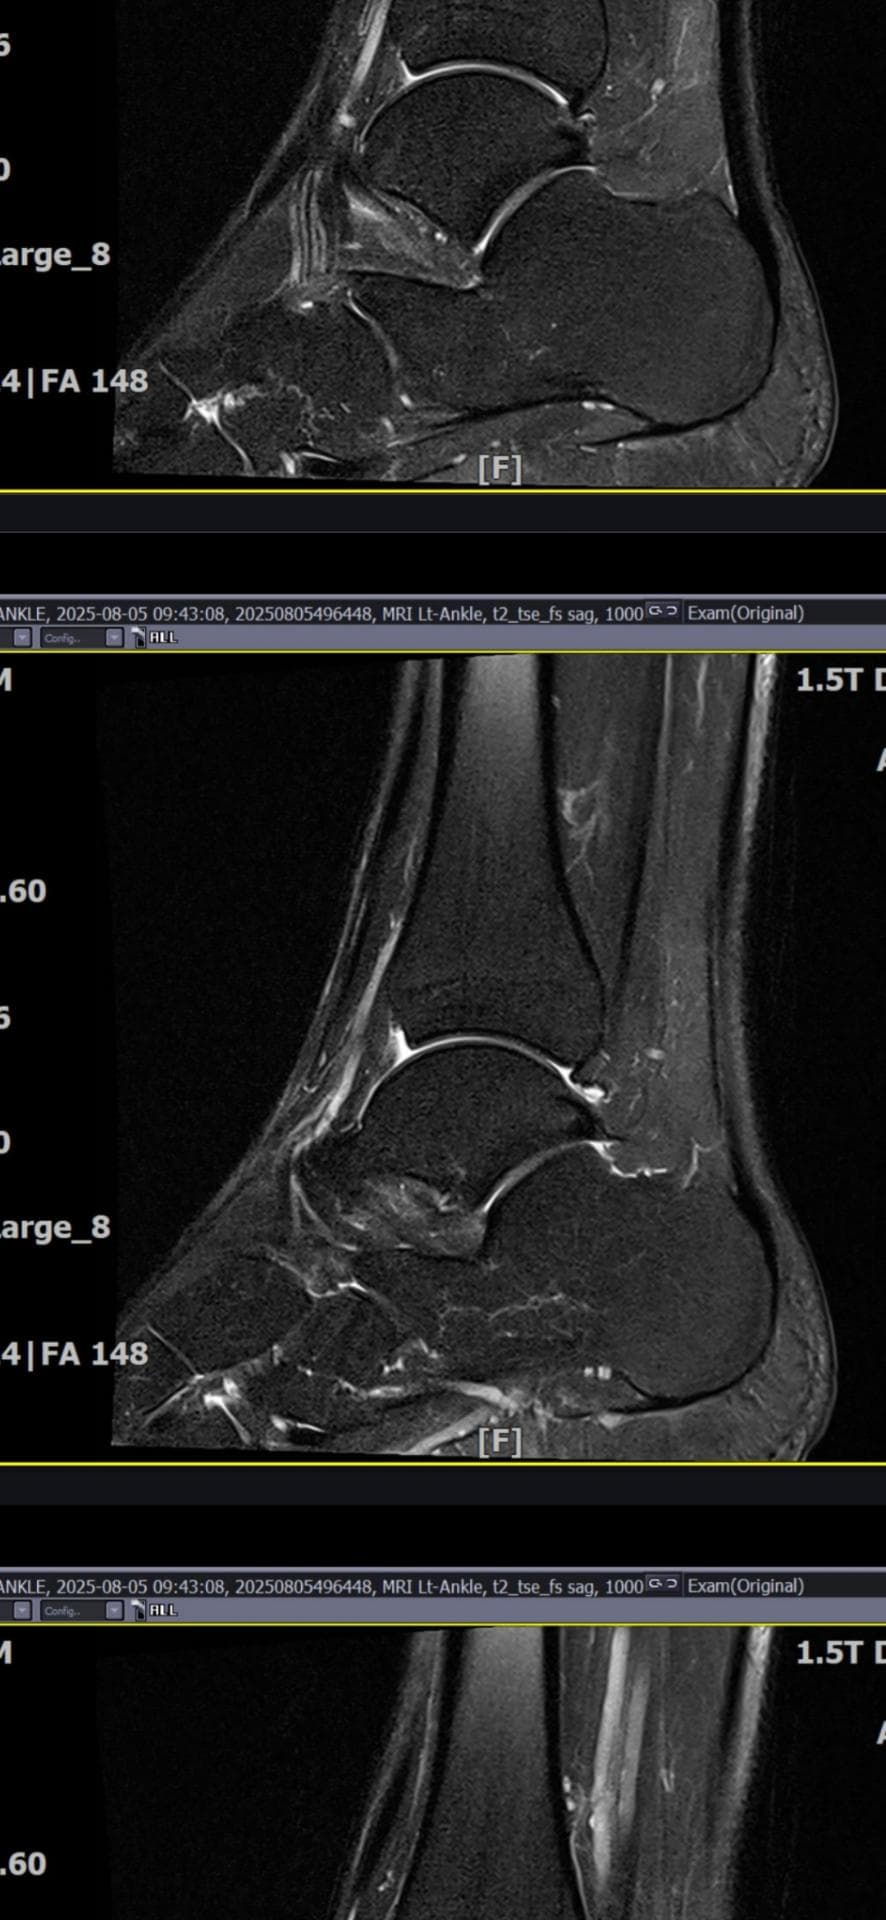

그래도 통증이 남아 8월 5일에 MRI를 촬영했는데, 병원에서는 “인대는 이어져 있고, 이 정도면 재활운동으로 호전될 것”이라는 설명을 들었습니다.

MRI 상 전거비인대와 발목 상태가 정말 회복 단계인지, 아니면 만성으로 넘어가는 건 아닌지 전문가분들의

의견을 듣고 싶습니다.

올려주신 mri를 보면 전거비인대는 연속성이 유지되고 있고 파열이나 큰 손상 흔적은 없어 재활로 회복 가능한 상태로 보입니다 다만 3개월 가까이 활동 시 통증과 미열감이 남아 있는 것은 조직 회복이 아직 완전히 끝나지 않았거나 주변 연부조직 관절 움직임 제한 등으로 인한 과민 반응일 수 있습니다.

초음파와 비교하면 mri 상으로 인대 연속성이 확인되므로 심각한 악화나 재파열은 아닌 것으로 판단됩니다

MRI상에서는 인대의 회복이 이루어지고 있는 덧으로 보이지만 인대의 회복은 소요되는 시간이 오래 걸리고, 주변 근육의 약화나 기능 저하로 인해 통증이나 불편감이 지속될 수 있습니다.